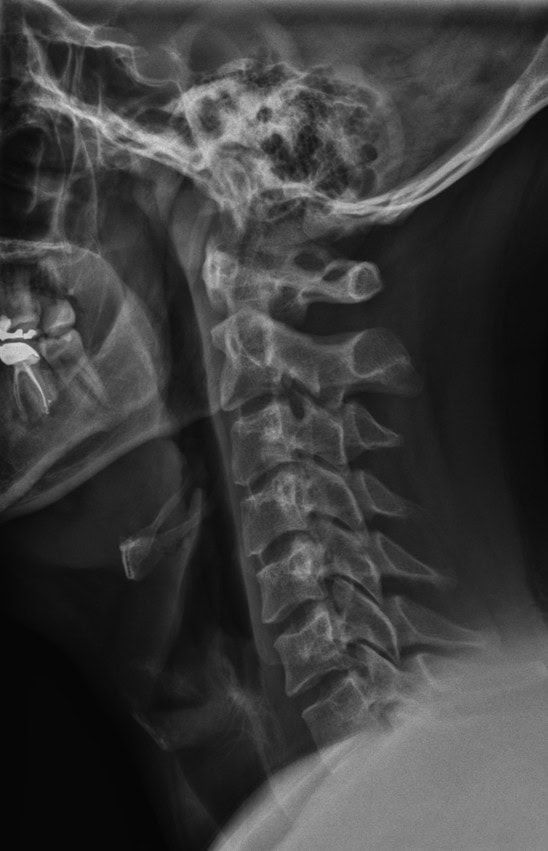

Kaylan’s journey with Maximize Chiropractic began back in 2015, when he came to us seeking relief from lower-back pain caused by an old snowboarding injury, along with persistent neck discomfort. Over the years, he dedicated himself to improving his health, including completing several sessions of Cranial Facial Release (CFR).

Through consistent care, Kaylan experienced significant improvement in his respiratory system, along with noticeable progress in his lower-back function, sleep quality, and overall energy levels. His commitment to his well-being has made a remarkable difference in his daily life.